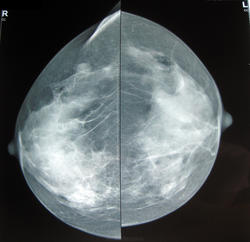

59 лет. Жалоб нет. Находка при профилактической маммографие. Ни чем особенным не болела.

фиброзно-кистозная мастопатия, Вас смущают шарики??? плотность у них прям стремится к металлической

В железе чисто, в проекции большой грудной мышцы какая-то мегахрень)

Не могут быть следы от дезодоранта?Там содержится свинец.

Свинец от дезодоранта обычно выглядит по другому: в виде россыпи мелких точечных интенсивных теней. А здесь в таком случае должна быть 2 см капля свинца.

А вот еще результаты УЗИ: слева в аксиллярной области эхонегативные образование, полностью поглощающее уз-сигнал, образующее за собой акустическую тень. Расположено в подкожно-жировой клетчатке, прилежит к коже.

Рядом - подозрительный л/узел, в воротах которого несколько гипоэхогенных образований.

Какие еще будут мнения о природе кальцината?

справа в верхне-наружном кв. возможно фиброаденома, а в аксилярной  области лимфоузлы с обызвествлением.